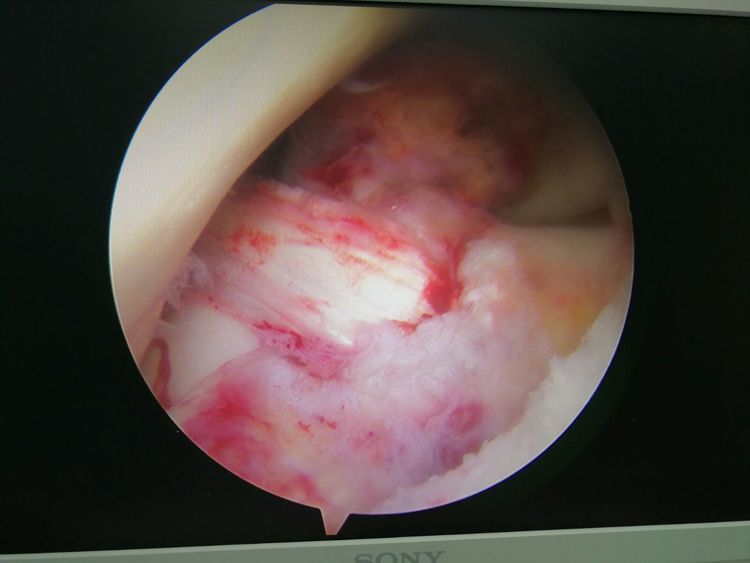

镜下手术图片,展示人体关节镜下情况:

骨科中心近两年共收治关节镜手术病人500余人,本人在近半年共收治关节疾病患者70余人,包括肩关节脱位及盂唇损伤、半月板损伤、交叉韧带损伤、叉韧带止点撕脱、髌骨脱位、色素性滑膜炎、关节游离体、老年骨性关节炎、踝关节外侧副韧带损伤伴距骨软骨损伤等。均通过关节镜或辅助关节镜手术治疗,短期内随访效果好,总体满意率在95%以上。

特别值的一提的是关节镜清理和韧带松解辅助关节腔注射治疗老年膝关节骨性关节炎效果明显,术后患者膝关节疼痛明显减轻,提高了生活质量,延缓了疾病的进展。当然术前查体及适应症的选择十分重要,患者的信任及配合,术前教育和术后康复指导也都是十分重要的。远期效果我会把随访结果分享给大家,希望大家共同关注老年膝关节骨性关节病!